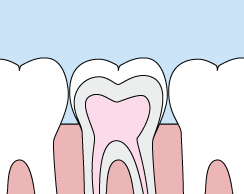

Crowns

crownsCrowns are a cosmetic restoration used to improve your tooth’s shape or to strengthen a tooth. Crowns are most often used for teeth that are broken, worn, or have portions destroyed by tooth decay.

A crown is a "cap" that is cemented onto an existing tooth and fully covers the portion of that tooth above the gum line. In effect, the crown becomes your tooth’s new outer surface. Crowns can be made of porcelain, metal, or both. Porcelain crowns are most often preferred because they mimic the translucency of natural teeth and are very strong.

Crowns or onlays (partial crowns) are needed when there is insufficient tooth strength remaining to hold a filling. Unlike fillings, which apply the restorative material directly into your mouth, a crown is fabricated away from your mouth. Your crown is created from your unique tooth impression in a lab. This allows a dental laboratory technician to examine all aspects of your bite and jaw movements. Your crown is then sculpted just for you so that your bite and jaw movements function normally once the crown is placed.